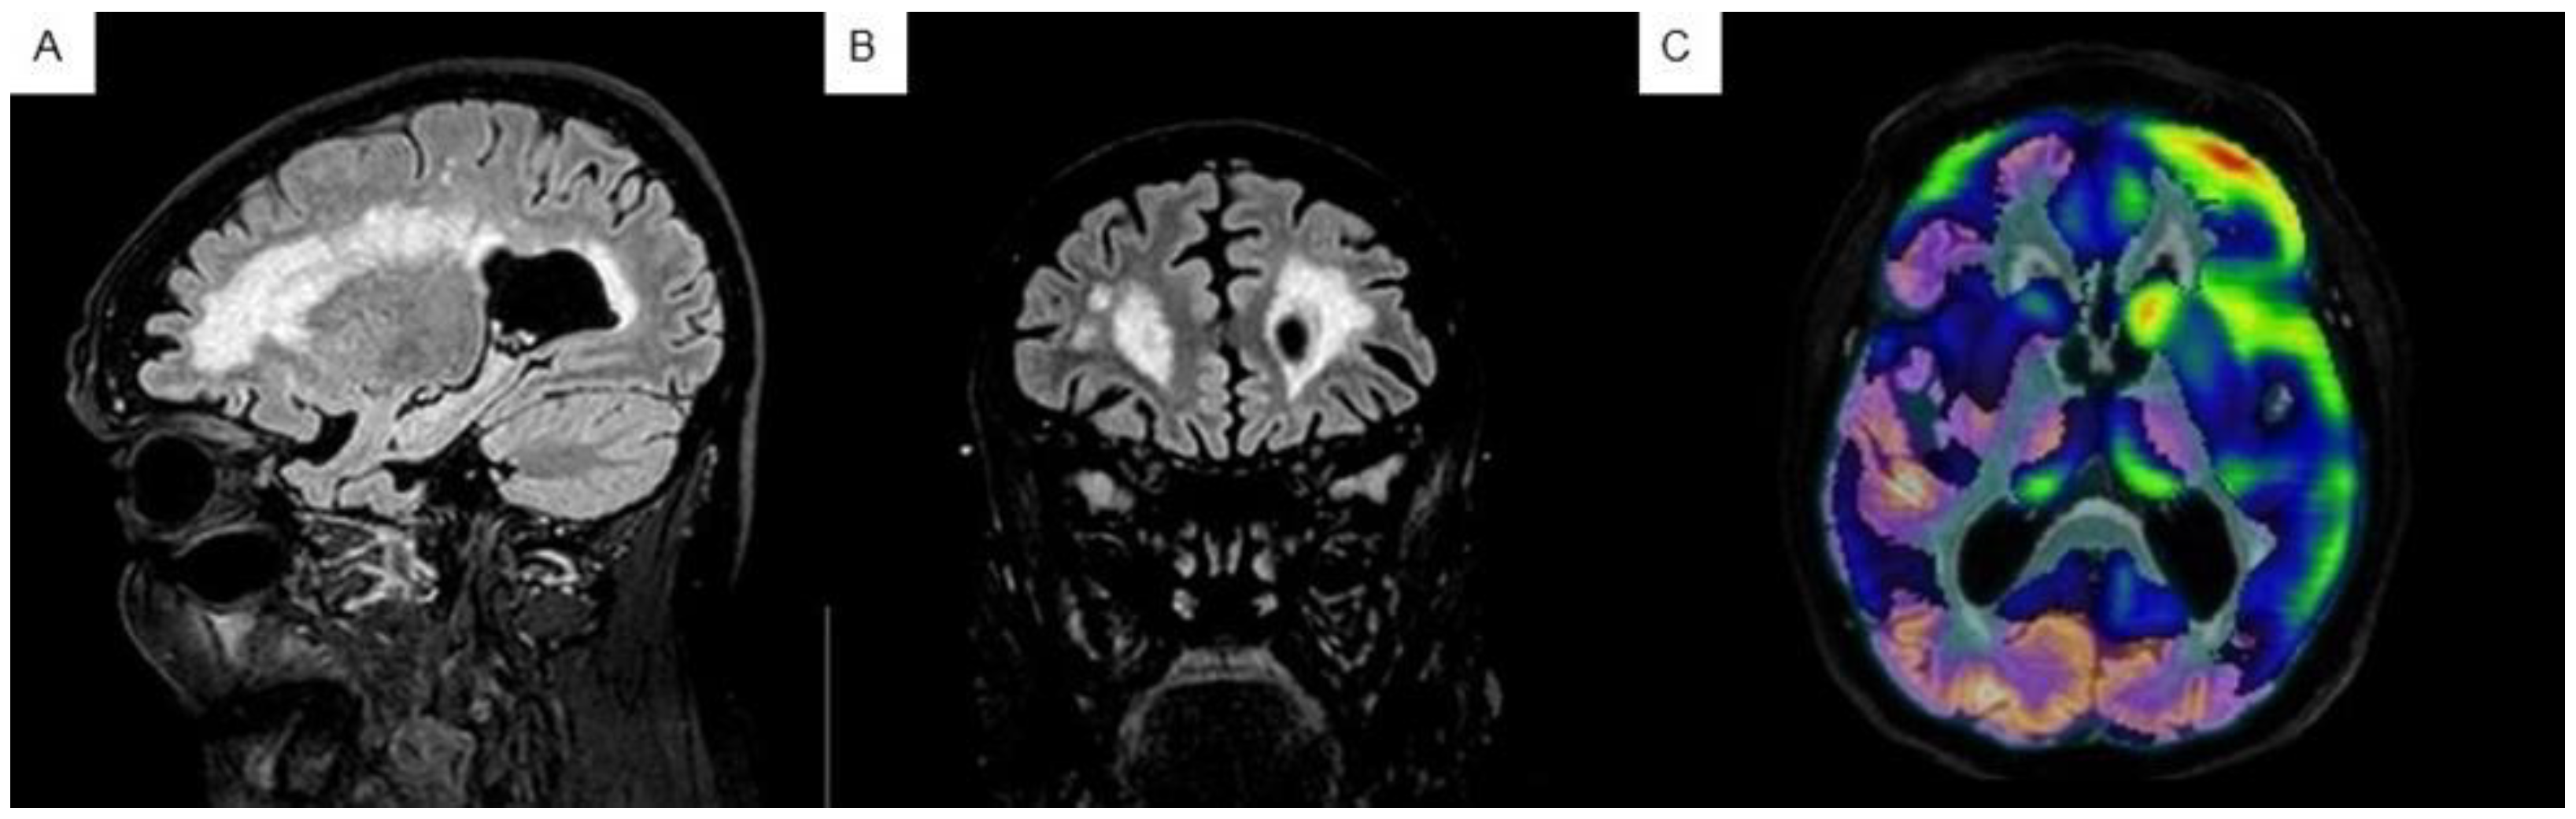

2.3.2. Neuroimaging Tests